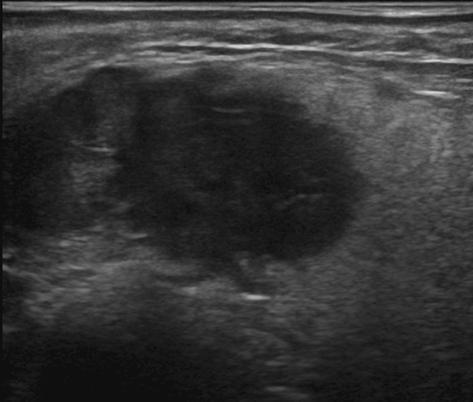

U tuyến nước bọt

» Thông tin: Nam giới – 72 tuổi.

» Lâm sàng: Khối vùng mang tai.

# Ung thư biểu mô tuyến (Adenocarcinoma).